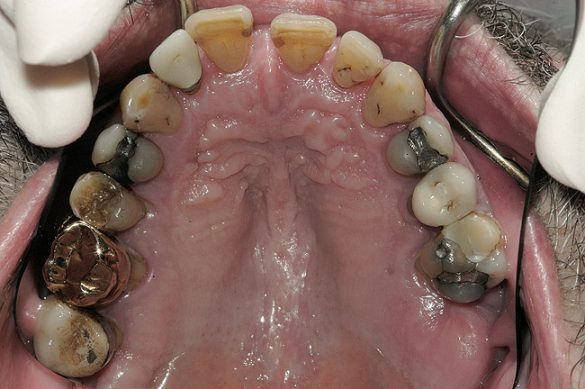

Obiective terapeutice

Consideraţiile privind managementul riscului şi planul de tratament au fost elaborate utilizându-se o abordare sistematică. Tratamentul ar fi redus riscul biomecanic prin eliminarea dinţilor compromişi structural (fig. 3,4), cu diminuarea concomitentă a riscului funcţional prin crearea unei ocluzii în armonie cu articulaţiile. În plus, tratamentul ar fi redus riscul parodontal prin îndepărtarea dinţilor irecuperabili, cu implicare parodontală, (fig. 5) şi ar fi îmbunătăţit estetica prin ridicarea cu 3mm a planului ocluzal pentru a minimiza expunerea gingivală şi a rădăcinilor.5-8

La examinarea clinică, o serie de dinţi prezentau restaurări directe mici acceptabile. Dinţii de la 1.7. la 1.4., de la 1.2. la 2.6., 3.6. şi 4.5. prezentau fie restaurări directe voluminoase, fie coroane cu acoperire totală, cu un grad ridicat de compromitere structurală. Nu s-au identificat leziuni carioase active. Implicarea pulpară era vizibilă la nivelul molarului 3.6.